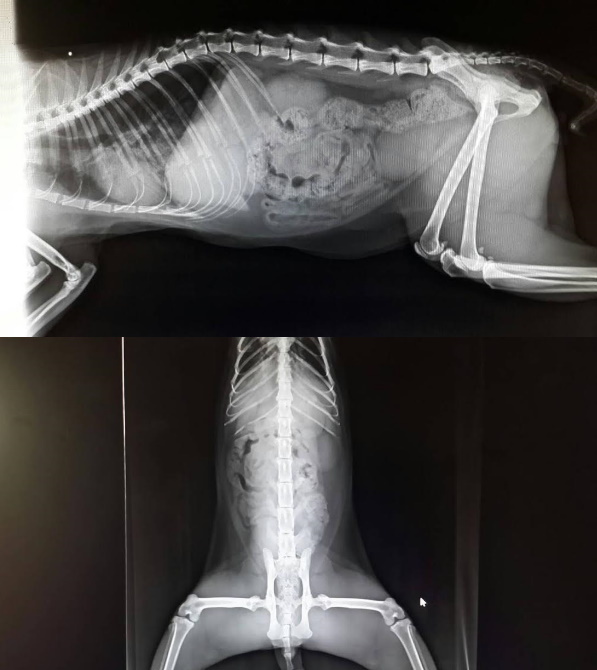

主題: 便秘+鼻氣管嚴的兩罐 申請者姓名: 臺北市支持流浪貓絕育計劃協會 花色: 申請日期: 2015-04-30 12:52:19 申請者部落格: 申請者臉書網址: 所在縣市/合作醫院: 台北市/欣旺動物醫院 治療費用: 13300元 需求人數: 15人 已結案 (2019-07-11 13:21:02) 報名人員: Daniel Tsai(已付款)、張承歡、Sunny Chen(已付款)、Tsai Dobbie(已付款)、Alisa Huang(已付款)、戀糖bear(已付款)、Mia Chao(已付款)、歐坤龍、Andrea(已付款)、蘇洛克(已付款)、Moon(已付款)、Yixiun(已付款)、ERic YU(已付款)、karyn(已付款)、風影(已付款)、田山胞(已付款)、fang7880(已付款)、 候補人員: 動物病情說明: "兩罐"協會門口的食客,每次都要吃兩個罐頭而命名,4月初看兩罐雙眼紅腫,精神萎靡,走路都慢慢的,用網子捕捉,送醫檢查血檢數值尚可,紅白血球肝腎指數正常,體重4.6公斤,蛋白比較低有,慢性發炎的貓都會這樣,鼻氣管炎較為嚴重,送驗卡里西等病毒,剛開始兩罐都不願意進食,狀況看起來很不舒服,噴霧和皮下點滴補充他越來越有精神,但鼻塞還是很嚴重,第四天,發現兩罐都沒有便便,給予一些化毛膏,第五天...還是沒有排便,灌食大量軟便劑,第六天晚上排出驚人便便,想必走路很緩慢是因為便秘,而鼻氣管炎和便秘讓他吃不下東西,每天噴霧、打水、灌食軟便劑讓便便能夠順利排出,慢慢狀況恢復正常,也有心情把自己舔的乾乾淨淨,沒事還在籠子內睡得東倒西歪,人一靠近,他得維持街貓的驕傲,又張牙舞爪的,慢慢兩罐鼻氣管炎痊癒,卻又發現她兩天沒有便便,要灌食軟便劑時,恢復健康的兩罐,無情的毆打醫師的防咬手套,力道十足,開始將軟便劑加在罐頭給兩罐吃,並照了X光發現兩罐腸道非常寬,應該有長期便秘的問題,日後照顧都需要在食物裡添加礦物油軟便劑,維持暢快人生,醫療費用還請各位幫忙。